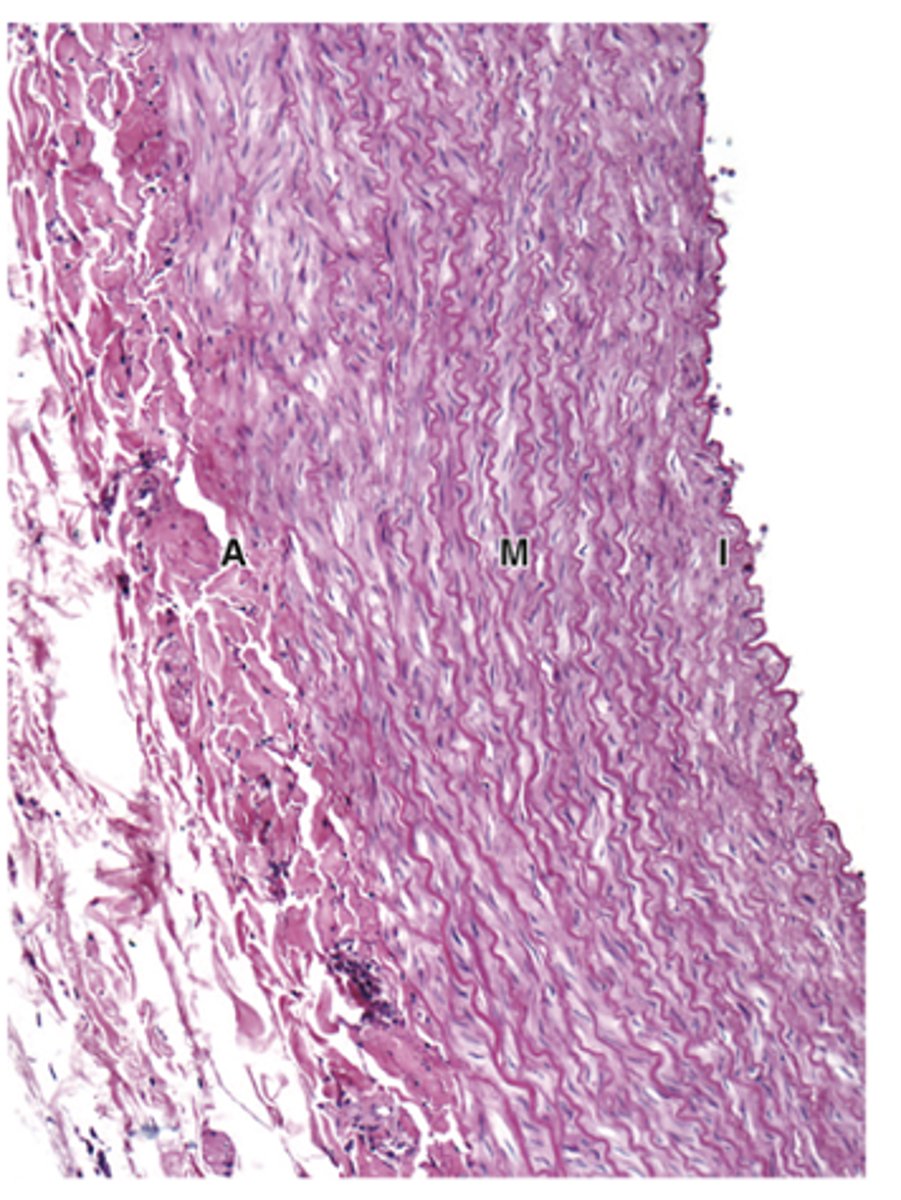

What is the composition of the tunica media and how does its thickness compare in arteries and veins?***

Smooth muscle and other varying components; thicker in arteries than in veins***

How are smooth muscle fibers arranged in the tunica media?***

Concentric, helically arranged layers.

In which vessels is the tunica media prominent with elastic lamellae?***

Only in arteries.

How does the tunica media in arteries compare to veins?

Thicker and contains much more elastin in arteries.

Thick, with fenestrated elastic lamellae alternating with layers of smooth muscle fibers.